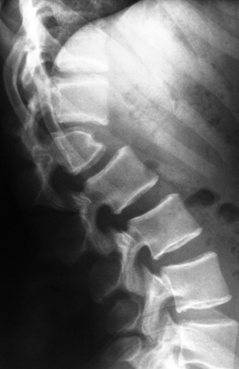

A l’examen du rachis dorsal, vous trouvez une déformation de la jonction thoraco-lombaire avec une cassure de la courbure.

Cette anomalie ne lui procure aucun problème, n’évolue pas depuis longtemps mais n’a jamais été explorée.

Vous demandez une radiographie